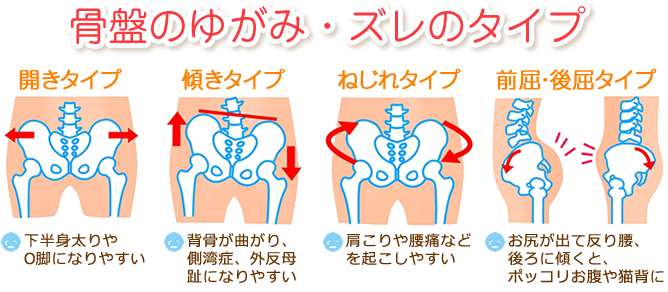

くことにより吸収され、 弱められる。あぐら姿勢で手を膝に置く場合、肘 関節が90度程度に屈曲する。このためあぐらでは、肘関節が身体の揺 れに合わせて動きやすく、呼吸などによる揺れを相殺する働きをしたの ではないかと思われる。あぐらをかいた時に、脚が床につかず、浮いてしまう。両手で膝を押し下げようと頑張っても、脚に力が入り、曲がらない。 あぐらをかいた時、脚が浮いてしまう?/photo by Kentaro Abe 股関節が硬いタイプが苦手なポーズ 股関節が硬い人が苦手なポーズ唱題の姿勢|願い方次第で必ず叶う勤行・題目 について 朝晩の勤行の時に、まず真剣に願いをかけるのです。 自分が願いたいことを順番に紙に書いて、勤行の後の題目の時に、一つずつ自分の生命に叩きこむように真剣に願うのです。 例えて言うなら

股関節の片方だけが硬い時 原因と簡単な改善法 府中オステオパシーまるちゃん整体院

日常生活で よくあぐらをかく人は腰痛になりやすいのか らいおんハート整骨院グループ

股関節が柔らかい人は 骨盤美人 開脚の柔軟性を高めるメリットとストレッチ方法8選 きたのっちストレッチ Qitano Stretch

股関節の片方だけが硬い時 原因と簡単な改善法 府中オステオパシーまるちゃん整体院

胡坐 あぐら と腰痛の関係 スポルト鍼灸整骨院 中野店 スポルト鍼灸整骨院 中野店

胡坐 あぐら と腰痛の関係 スポルト鍼灸整骨院 中野店 スポルト鍼灸整骨院 中野店

股関節が柔らかい人は 骨盤美人 開脚の柔軟性を高めるメリットとストレッチ方法8選 きたのっちストレッチ Qitano Stretch

股関節が柔らかい人は 骨盤美人 開脚の柔軟性を高めるメリットとストレッチ方法8選 きたのっちストレッチ Qitano Stretch

胡坐 あぐら と腰痛の関係 スポルト鍼灸整骨院 中野店 スポルト鍼灸整骨院 中野店